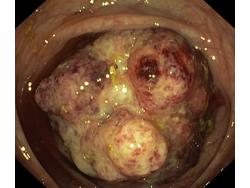

Nowotwory przewodu pokarmowego